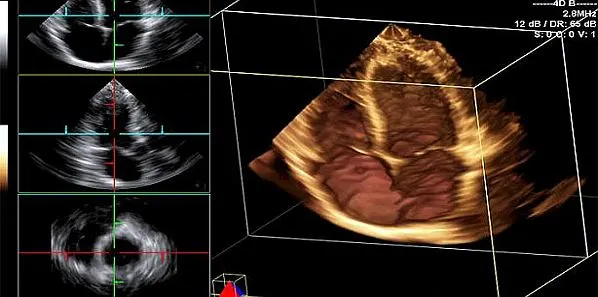

The most common heart imaging tests involving radiation include computed tomography (CT) scans, such as coronary artery calcium scores and CT anagrams of the heart, fluoroscopy, and nuclear medicine tests, such as the nuclear stress test. Exposure to radiation is linked to an array of side effects, such as diarrhoea, vomiting, internal bleeding, damage to the central nervous system, cancer, and even death.